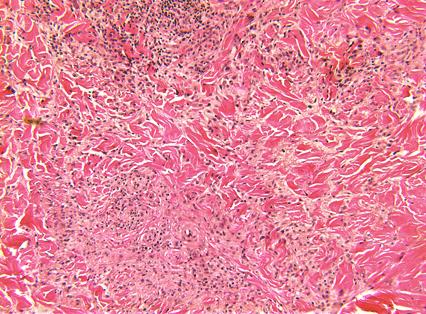

栅栏样模式:特征为真皮中上层淋巴组织细胞炎性浸润,而炎性浸润呈栅栏样包绕胶原及弹性蛋白变性区域。胶原变性区域表现为嗜酸性纤维物质被嗜碱性黏蛋白沉积物所分隔。也可能存在嗜酸性粒细胞。

图:上部坏死区显示微弱的嗜碱性粒细胞,代表细胞、纤维、嗜酸性粒细胞物质束间的粘液变性。边缘见组织细胞和一些淋巴细胞,伴有正常胶原的完全粘液变性 (HE 400x).